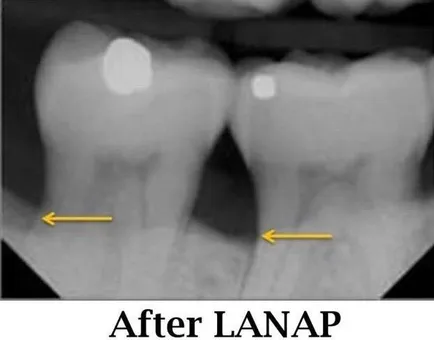

LANAP® and LAR both utilize the PerioLase® MVP-7™, a specialized dental laser that targets and destroys harmful bacteria while leaving healthy tissue intact. The procedure stimulates the body’s natural ability to regenerate bone and connective tissue, helping gums reattach to the teeth.

• FDA-cleared regeneration: LANAP is the only laser protocol cleared by the FDA for True Periodontal Regeneration, including new bone growth.

• Tooth-saving: Many teeth that were once considered hopeless can now be saved.